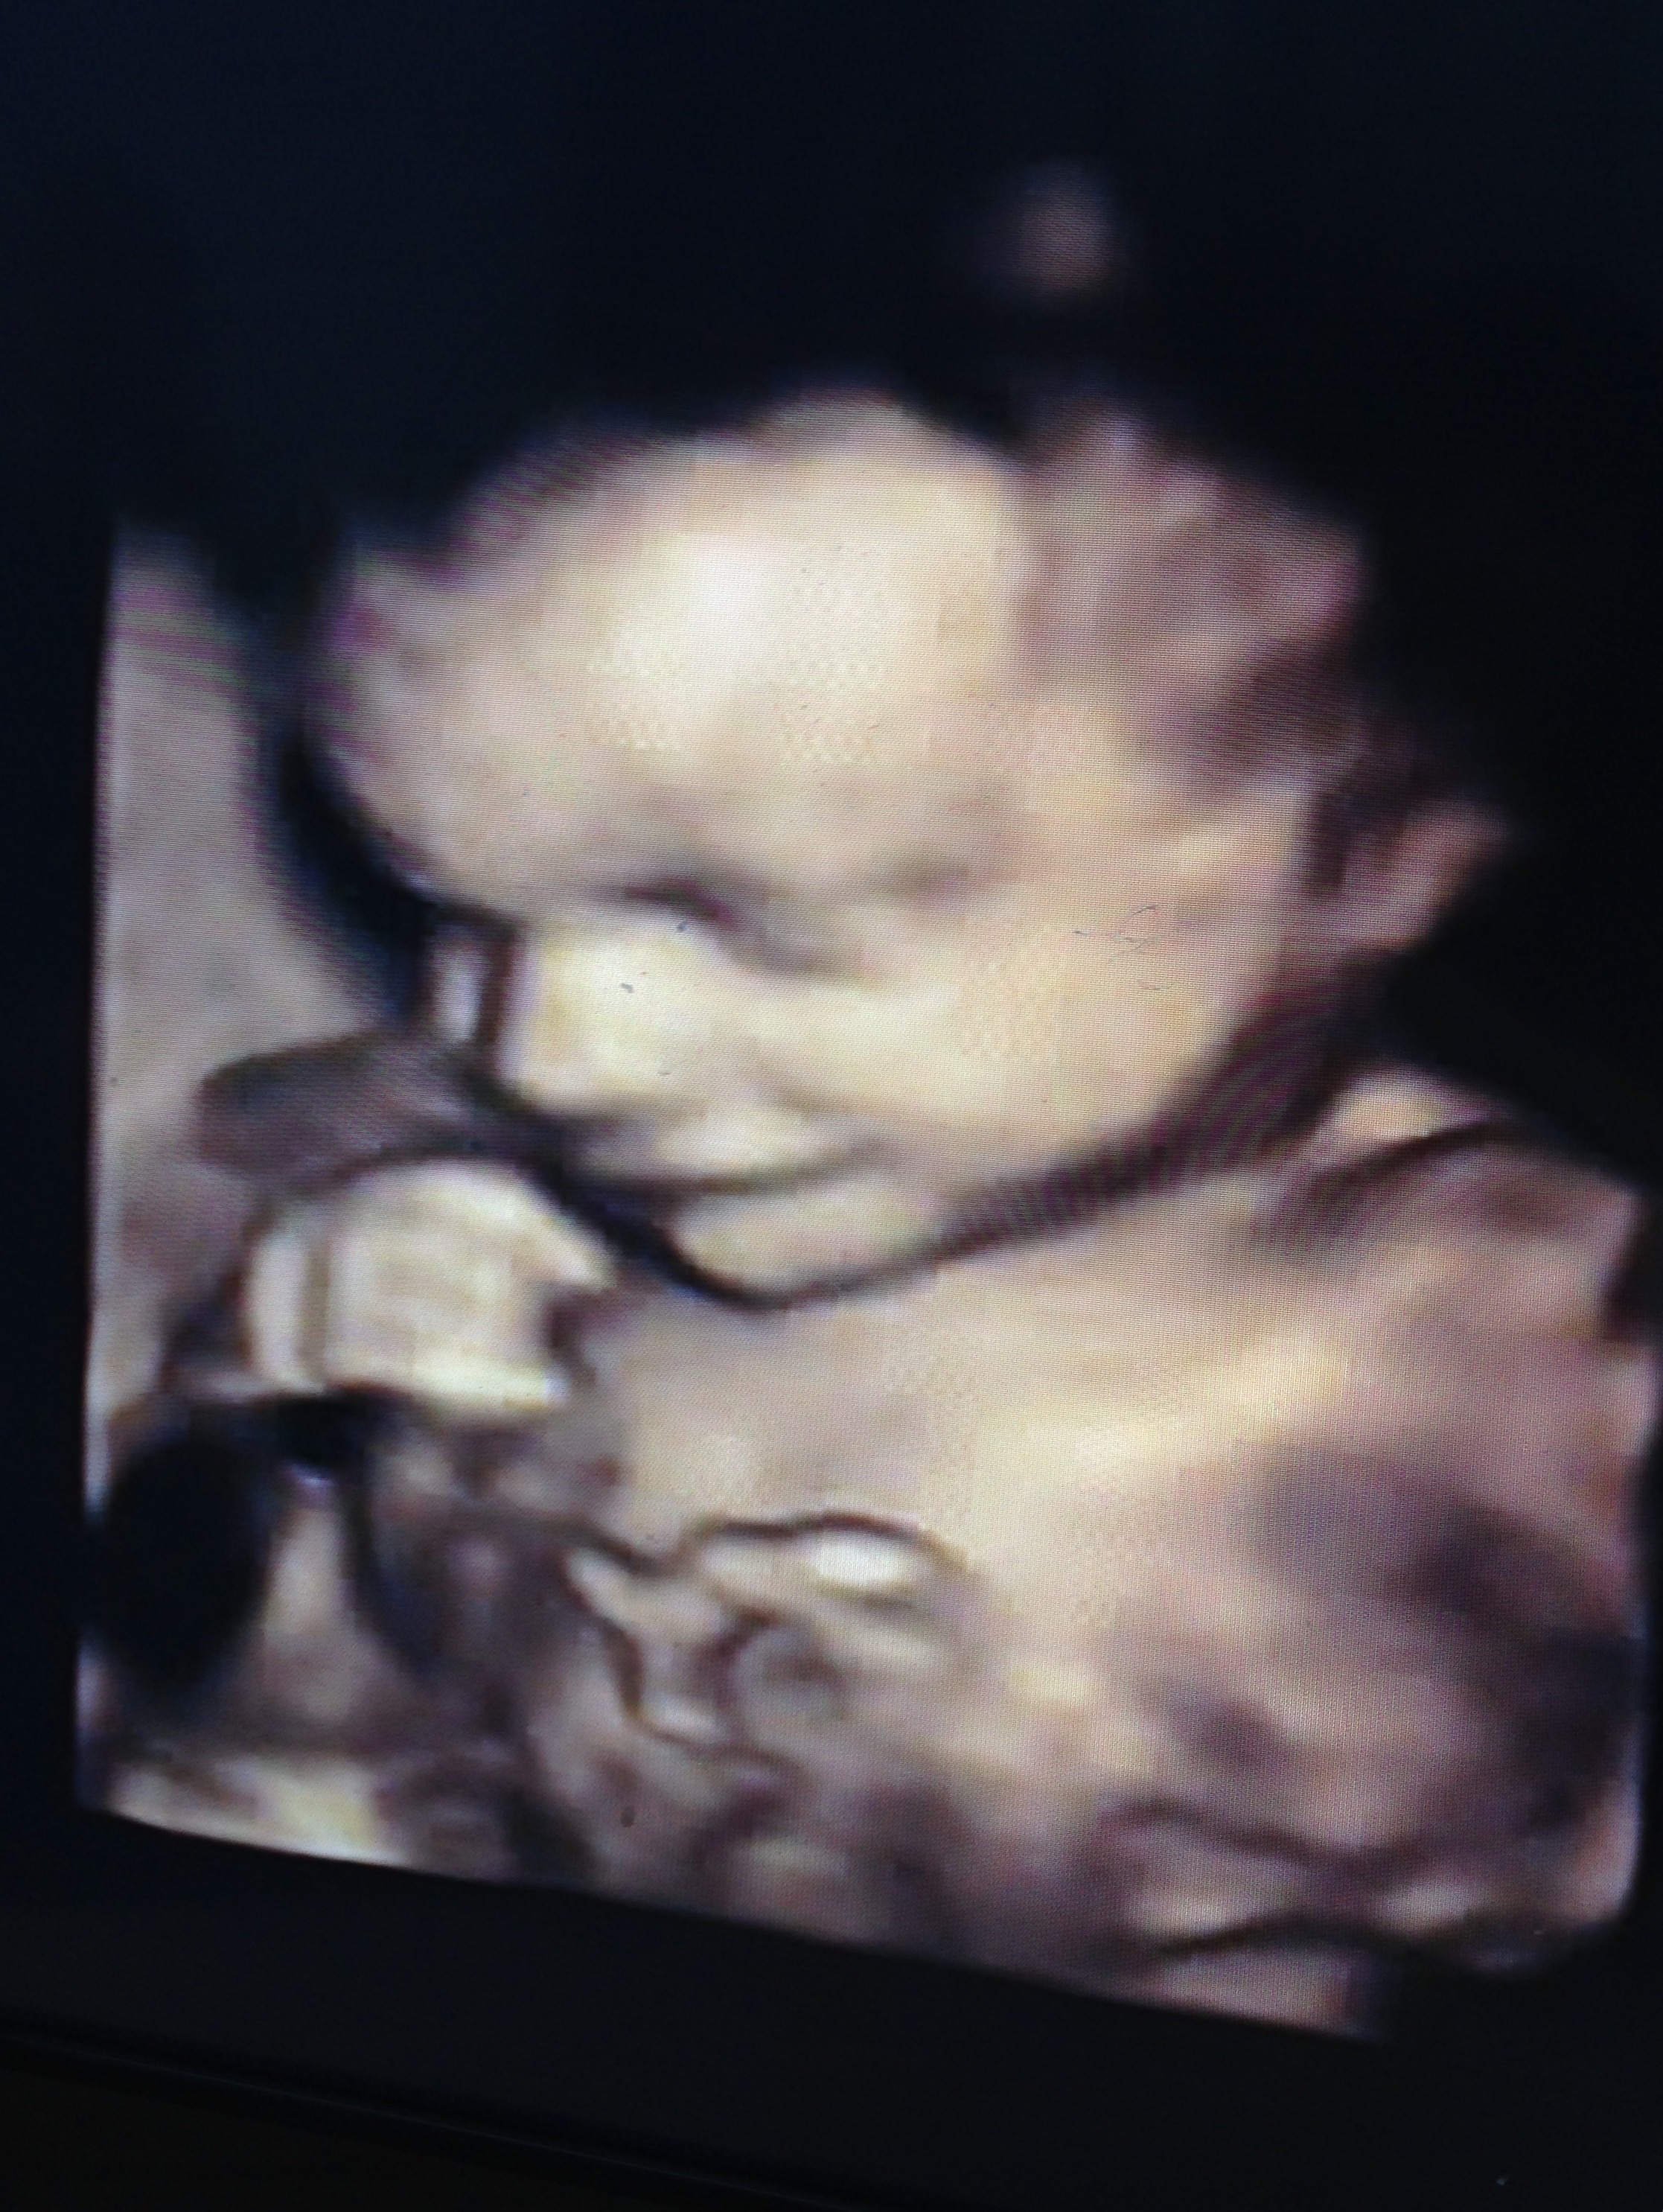

I reacently went for a 4d scan, i went when I was 26 weeks 1 day.

When they measured my boy he meausured at 28 weeks 2 days, does this mean my due date could be wrong? What's people's experiences?

Here's my big boy <3